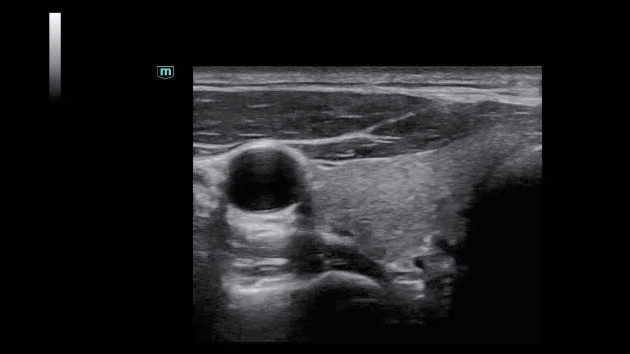

ZST+ ??? ???? ?? ???

ZST+ ???? ???? ??? ???? ??? ?????. ??? ???? ?? ? ???? ?? ??? ?? ??? ?????. ??? ??? ? ?? ??? ??? ???? ?????? ??? ???? ???? ??? ?? ?? ?? ?? ???? ?? ??? ?? ??? ?????.